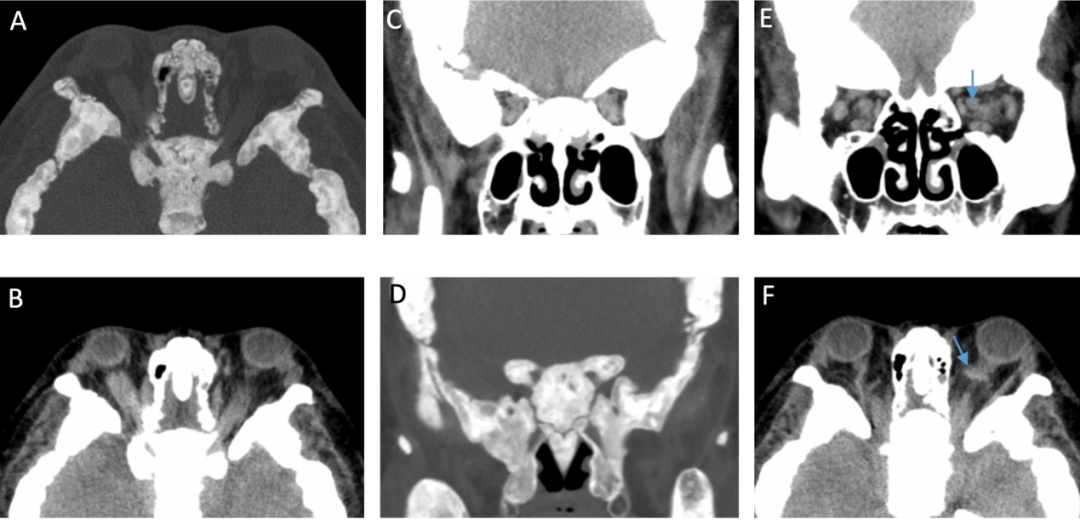

近日,“医学界”从上海交通大学医学院附属第九人民医院(下称“九院”)获悉,该院诊断出一例发病率仅百万分之一的罕见遗传性骨病。据了解,这是一名年轻女性,因双眼突出及视力下降,前往九院眼科就诊。除眼部异常外,她还同时伴有长期四肢骨痛、听力下降等全身表现。接到患者后,九院眼科迅速组织内分泌科、分子诊断科、骨科、影像科、耳鼻喉科等开展多学科联合会诊,最终确诊为Camurati-Engelmann病(进行性骨干发育不良)。该病例研究已于近日在国际眼眶病领域权威期刊Orbit在线发表。据介绍,患者以双侧眼球突出伴视力下降为主要表现,同时存在长达15年的四肢骨痛及听力进行性下降。曾于外院诊断为甲状腺功能减退症及性腺功能低下。眼科检查发现,患者存在双眼上方视野轻度缺损,伴有视神经纤维层变薄。此外,眼眶CT还提示患者的视神经受压。CT显示,患者双侧眼眶骨壁弥漫性增厚,眶尖区域明显狭窄,同时可见视神经管变窄及眼上静脉扩张(见下图蓝色箭头)。这些改变提示,眶尖拥挤导致视神经受压,静脉回流受阻可能加重眶内压力,进而影响视神经供血及视觉功能。进一步全身X线检查显示,患者全身多处长骨存在双侧对称性骨干皮质增厚、骨性膨大,提示疾病并非局限于眼眶,而已经累及全身骨骼系统。从家系图可以看出,患者家族中共有包括其母亲的9名成员存在类似表现,呈现明显的家族聚集现象,提示该疾病的遗传背景。基因检测进一步证实,患者及其母亲均携带TGFB1基因致病性变异。该基因编码转化生长因子β1,在骨重塑调控中发挥关键作用,其异常可导致骨形成与吸收失衡,从而引发特征性骨干增厚。结合临床表现、血液学、影像学及遗传学证据,最终确诊为Camurati-Engelmann病。经多学科会诊,鉴于患者目前视力情况尚稳定,优先针对骨代谢异常及内分泌紊乱予以系统性治疗,并进行密切随访视功能变化。若随访过程中出现进行性视力下降或视神经损伤加重,可考虑行眼眶减压术及视神经减压术,缓解视神经压迫。值得注意的是,患者母亲在妊娠及分娩后症状曾出现明显缓解。类似现象在既往个案报道中亦有描述。提示疾病可能与激素水平变化或免疫调节机制相关,但具体机制仍有待进一步研究验证。研究作者介绍,Camurati-Engelmann病是一种罕见的常染色体显性遗传性骨代谢疾病,主要由TGFB1基因突变引起,发病率约为1/100万。其典型特征为长骨骨干皮质对称性增厚及骨重塑异常。典型临床表现为四肢骨痛、肌无力及步态异常,可伴随内分泌功能异常等全身表现。随着疾病进展,病变可累及颅骨与颅底结构,导致头痛、听力下降及视功能损害。该病临床表现异质性较大,容易造成误诊或漏诊,临床上通常需开展多学科联合诊疗,以明确诊断并指导后续治疗。上海交通大学医学院附属第九人民医院眼科周慧芳教授与内分泌科乔洁教授担任共同通讯作者,眼科博士研究生雷超宇为第一作者。分子诊断科赵双霞副研究员及眼科李寅炜副主任医师共同参与了疾病诊治和研究指导。